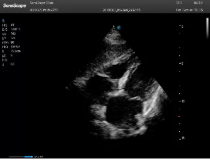

不同的探頭對應(yīng)于不同的臨床領(lǐng)域,不同的探頭頻率也應(yīng)用于不同的人體組織。超聲波在人體中的衰減與探頭頻率有關(guān),探頭頻率越高,穿透力越弱,分辨率越高,而探頭頻率越低,穿透力越強,分辨率越低。因此在檢查淺表器官時應(yīng)選用高頻探頭,而檢查深部臟器時則選用穿透性強的低頻探頭。

Mark點:每一把探頭都有一個mark點,是用于定位方向, mark點一側(cè)始終對應(yīng)著圖像S點(圖像箭頭標(biāo)識)一側(cè)。